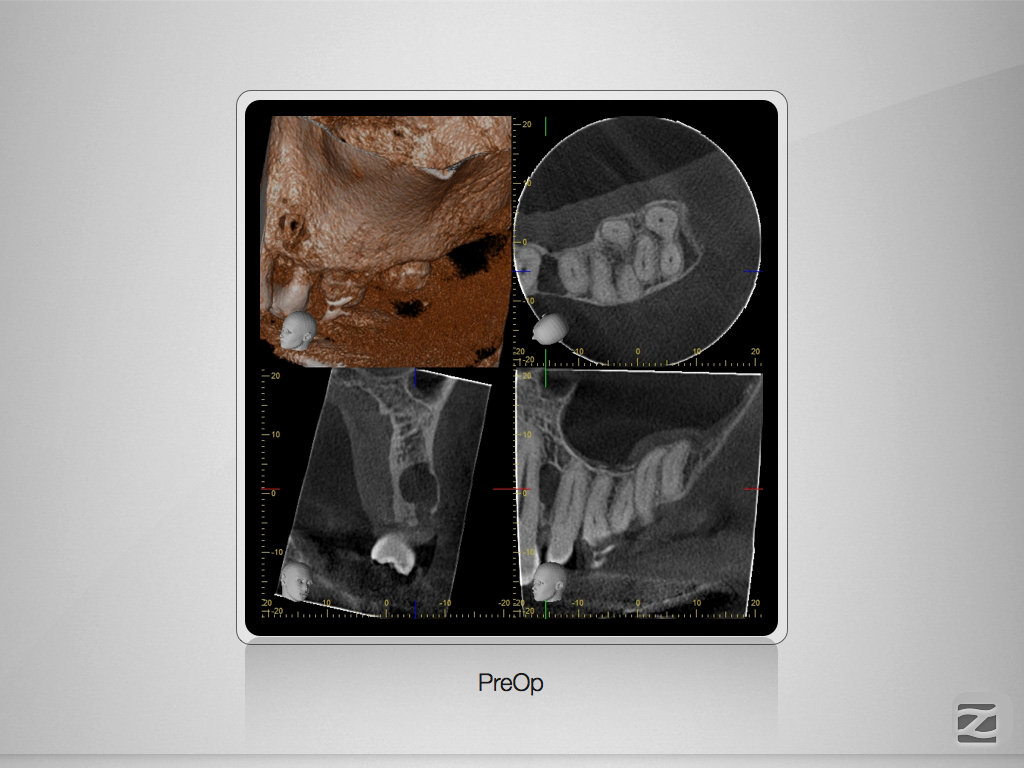

27D.003

Hyflex Fallbeispiel (3/3)